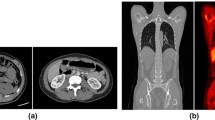

Overall analysis time per scan incorporating the manual segmentation method was approximately 4 h compared to ≤ 30 min when AI-based segmentation was used. Example patient images, including whole organ segmentations, are shown in Fig. 1. A comparison of organ volumes obtained using the two different segmentations methods is illustrated with scatter plots in Fig. 2. The segmented volumes using manual and AI-based segmentation in the kidneys (P = 0.005), in the liver (P < 0.001), and in the spleen (P < 0.001) were significantly different. Median Jaccard similarity coefficients between manual organ VOI segmentations and AI-based segmentations varied from 0.05 (range 0.00–0.14) for the pancreas to 0.78 (range 0.74–0.82) for the lung. A complete overview of Jaccard similarity coefficients is provided in Table 1.

The manual segmentations performed in this study showed some inaccuracies, for example, inclusion of a small part of the inferior vena cava in the liver segmentation, and exclusion of the border of the kidney, see Fig. 1. Also, the AI-based segmentations showed imperfections, for instance in the kidneys, spleen, and pancreas as can be seen from Jaccard values (Table 1), in Fig. 4, and Supplemental Fig. 1. This pilot study showed however that effective dose estimation is accurate (within 2%) regardless of these variations in manual or AI-based organ segmentation. Since whole-body dosimetry involves the summation of weighted dose values from multiple organs and structures, effective dose calculation is less susceptible to variabilities that arise by the type of segmentation method.

The low-dose CT dataset used in the current study showed streak artifacts in some cases. Example images, including whole organ segmentations, are shown in Fig. 4. These were the cases in which the pancreas was not accurately segmented by the AI-based tool, but also the kidneys, liver, and the spleen showed differences in segmented volume. These volumetric differences did not lead to inaccurate effective dose estimates in this small dataset. However, for smaller or other antibody moieties, accuracy and precision of organ segmentation may be more critical to obtain reliable dose estimates. The developers of the tool confirmed that in the training set of the CNNs, no image artifacts, such as streak artifacts observed in our data, were included. To overcome these issues in future work, a convolutional neural network could be trained to handle these data, including streak artifacts. At this time, we recommend that AI-based segmentations should be supervised by an observer and corrected when needed. Nonetheless, with respect to manual delineation, a considerable amount of time can be saved by supervised AI-based whole organ segmentation.